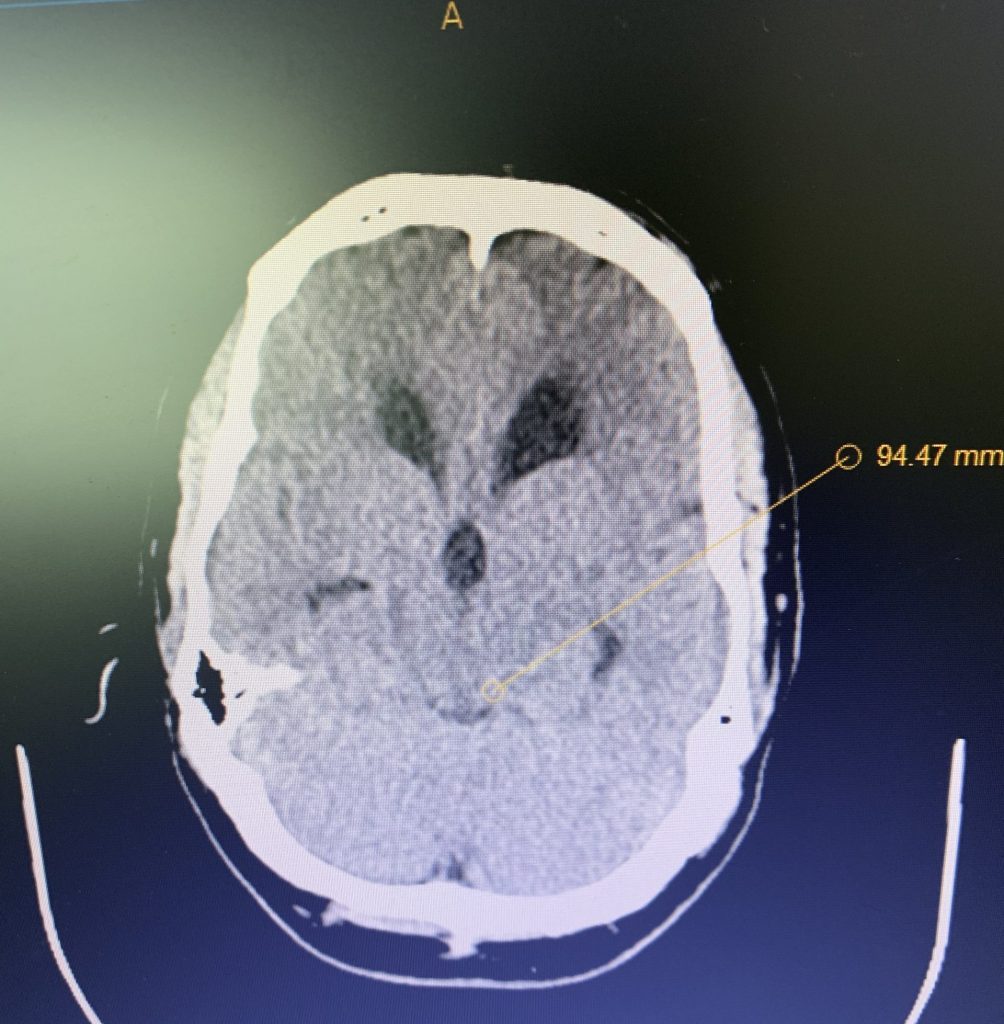

On initial examination, the patient was neurologically intact without complaints of headache. His imaging; however, did show hydrocephalus, most notably the lateral and third ventricles with a normal sized fourth ventricle. Given that the patient had no complaints, a decision was made to follow this expectantly and he was referred for a neuro-ophthalmologic evaluation, which confirmed no evidence of papilledema. MRI was otherwise negative.

Figure 1B,C: Pre-operative CT images.

Prior to shunting, a head CT was obtained and the head CT in addition to documenting a patten of obstructive hydrocephalus suggested a possible mass lesion compressing the aqueduct at its inferior aspect. Figure #1 demonstrates the hydrocephalus and the possible lesion. A decision was made at this point that the patient had obstructive hydrocephalus that was now symptomatic and he was taken for a laparoscopic-assisted ventriculoperitoneal shunt.